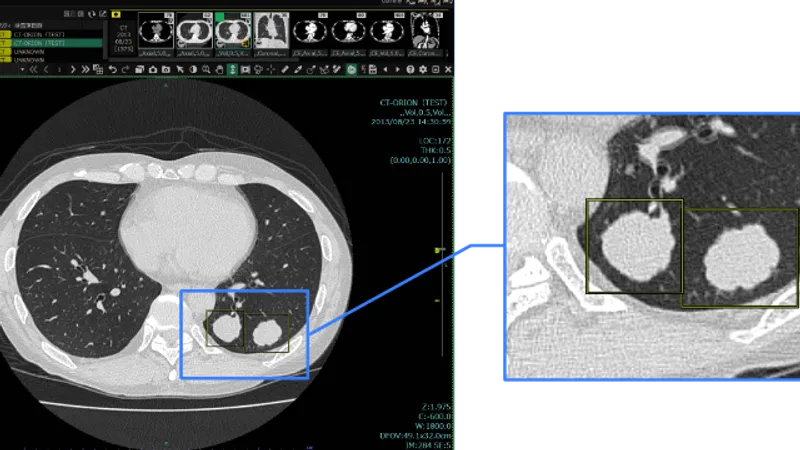

胸部CT画像から肺結節の候補を検出して表示する機能です。医師が再確認することで、見落しを低減します。

本製品の特長は以下3点です。 ① 胸部CT画像から肺結節の候補を自動で検出し、検出箇所をマークして表示します。医師は画像確認を行った後、マークされた箇所を再確認し、肺結節かどうかを判断します。 ② CT画像を3D解析する当社技術を活用し、3次元情報に基づいて肺結節の候補を検出するため、CTの断層画像だけでは見分けがつきにくい、血管に付着した結節等も検出することができます。 ③ 臓器認識技術により、肺領域を認識したうえで検出するため、胸壁に接した結節の検出も可能です。 また、SYNAPSE SAI viewer*1と併せてご使用いただくことで、結節のある箇所の肺区域ラベリングの結果を確認いただけます。 *1 SYNAPSE SAI viewer 販売名:画像診断ワークステーション用プログラム FS-V686型 認証番号:231ABBZX00028000 SYNAPSE SAI viewer用画像処理プログラム 販売名:画像処理プログラム FS-AI683型 認証番号:231ABBZX00029000